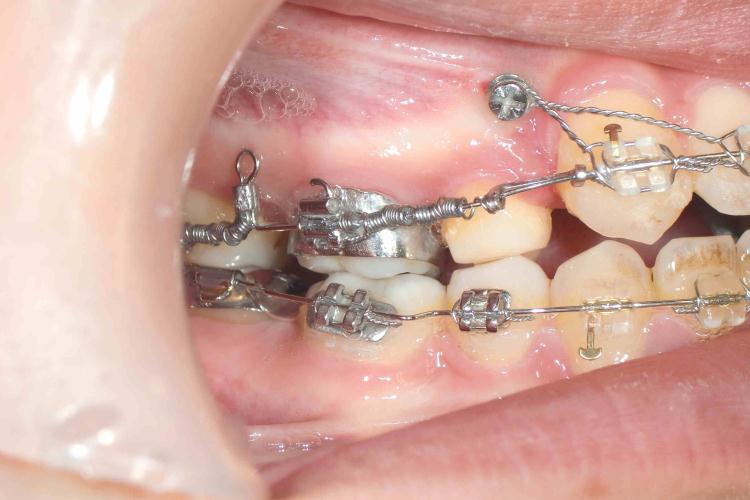

歯並びは正常な位置に生え揃うことが理想的ですが、さまざまな原因で下のように歯並びが乱れてしまう場合もあります。

矯正歯科の目的は、歯並びをゆっくりと美しく治し、心身が健康になることです。

矯正治療は長期にわたるために、治療に関するどんなことでも気軽に話し合いながら、丁寧にコミュニケーションをとりながら、正しい歯並びへと治療を進めてまいります。

矯正装置は種類も数多くありますが、当院では患者様の現在の状態やコスト面などにも考慮して、最適な治療計画を提示しながら治療を提供しています。